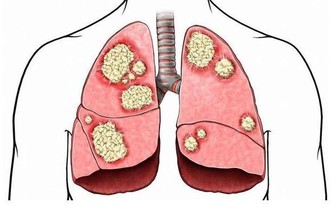

雖然說季節對於前列腺的功能影響很大,但其實,也佔據主要因素之一,

但事實上,之所以目前生活中前列腺炎非常高發,主要原因還是前列腺炎的病因非常常見,

比如性行為異常,或者是長期久坐但缺乏鍛煉等。